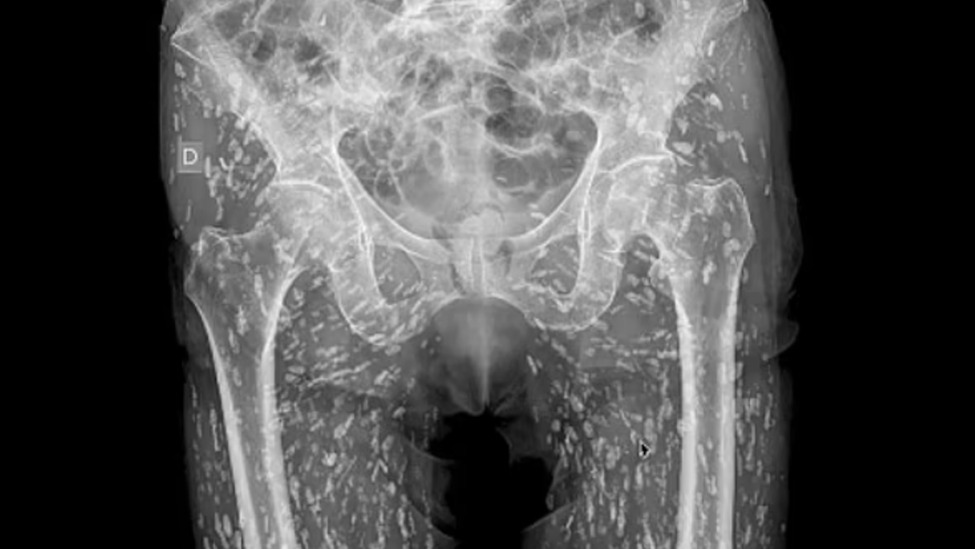

男子因误食未煮熟的猪肉,下半身遍布绦虫卵,X光片令人头皮发麻